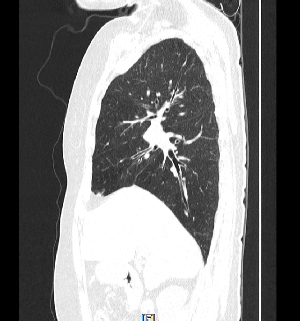

CT는 몸의 단면을 영상화하여 각종 질환을 진단하는 영상의학과 장비 중 하나입니다.

의료용 방사선을 이용하는 X-ray 검사와 비교할 때 인체의 해부학적 구조물이 겹쳐져 보이지 않고 인체의 축상면을 영상으로 획득합니다.

획득된 영상을 전산화된 프로그램을 이용하여 3차원(3D) 영상으로 재구성이 용이하며 인체의 시상면, 관상면 재구성도 가능합니다.

기존 X-ray검사에서는 진단이 불가능했던 질환을 더 자세하게 진단이 가능하게 하는 장비입니다.